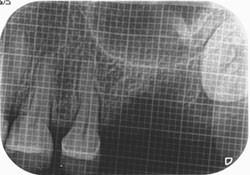

症例3【40代女性】右上74根尖病巣の治療 右上56 洞低膜を挙上しインプラント埋入

治療前

主訴 右上で物が噛めない。インプラントを希望され来院。

右上第二小臼歯はC₄にて抜歯。右上第一大臼歯は欠損の状態。

残存骨が5~6㎜程で、インプラント埋入には骨の高さが不足している為、ソケットリフト(骨造成)を行った。洞底膜を挙上することで、骨の高さの不足を解消。

採血のよるCGFメンブレンとAFGブロック(人工骨β‐TCPとAFGを混ぜたブロック)を填入しインプラント2本を埋入。約4ヶ月の免荷期間を経て、仮歯を装着、リハビリをし、約5ヶ月後にメタルボンド(金属焼付ポーセレン)を装着。

リスクとしては、ソケットリフト(骨造成)による一過性の副鼻腔炎が起きる可能性がある。まれに洞底膜が破れる可能性がある。ただし、膜は約3週で再生するので、膜の回復を待ち、再オペを行う。

費用 113万(オペ・ソケットリフト・人工骨・採血による濃縮血小板生成・仮歯・最終補綴物まで含む)